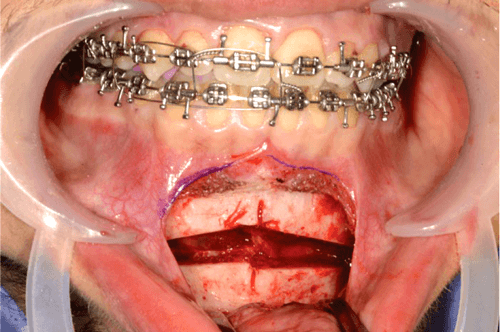

Using a surgical marker, the planned osteotomy line is marked at least 5mm inferior to the anterior tooth root apices (noting that the maximum average length of the canine tooth is 25-27mm) and the mental foramina. The chin midline is scored between the lower central incisors to ensure accurate symmetrical alignment during rigid fixation (Figure 2).

Figure 2.